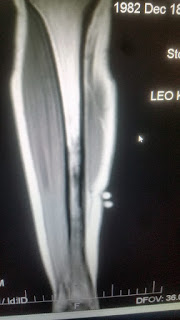

Here are a few of the images:

| Dark area is the stress site. |

| More contrast. |

| Cross section. |